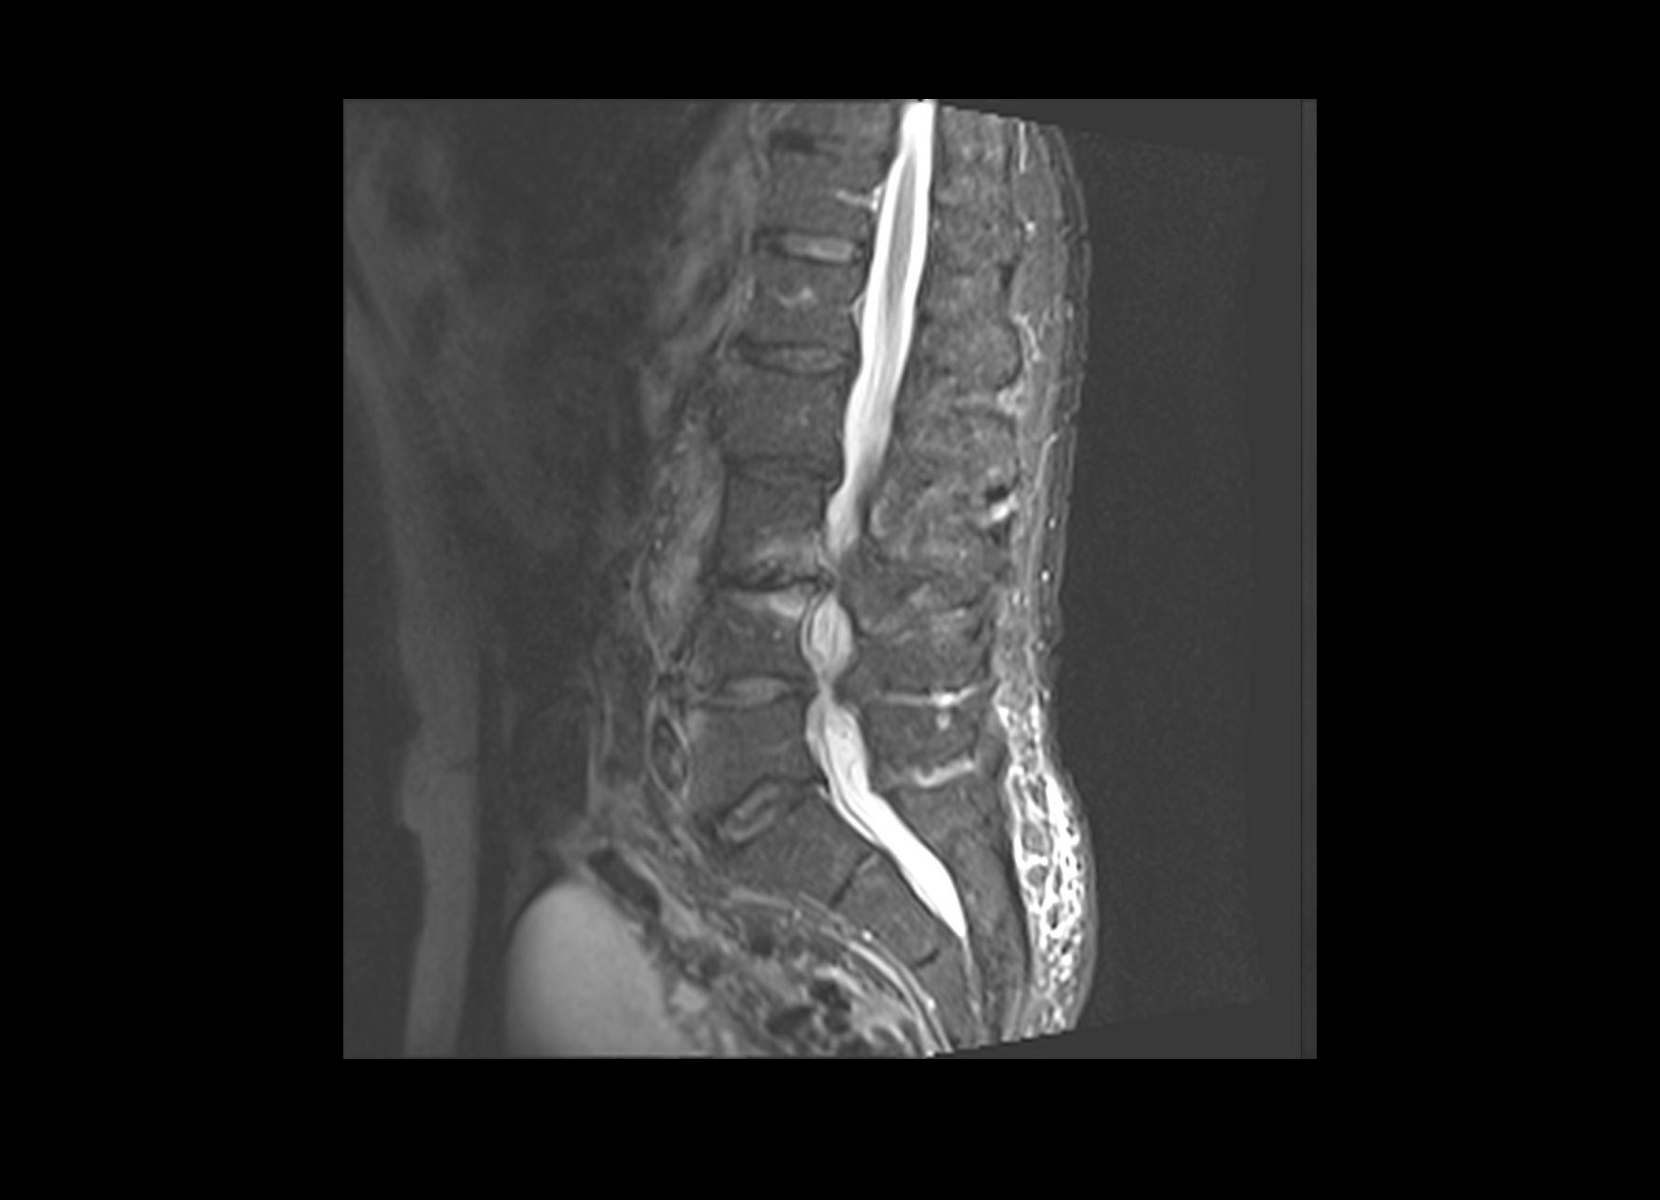

Conventional

STIR

SubtleSYNTH™

(Synthesized STIR)™

Vascular

GE 1.5T

C-spine